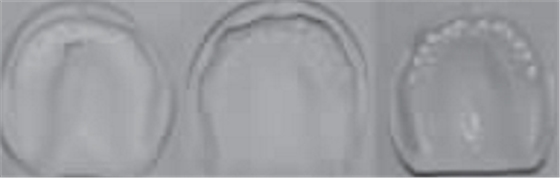

1.2.3治療過程:先行微創(chuàng)拔除14、13、21、22、23、24及25,搔刮拔牙窩去除炎癥組織,常規(guī)制作一副上頜過渡義齒(圖4,5)。2個(gè)月拔牙術(shù)后復(fù)診,利用上頜過渡義齒作為個(gè)性化托盤取上頜模型并翻制石膏模型,在石膏模型上根據(jù)過渡義齒標(biāo)出各個(gè)牙位,同時(shí)利用壓膜機(jī)制作放射性模板(如圖6)?;颊吲宕鞣派湫阅0迮臄z全景片及CBCT(如圖7、8)。

圖6 放射性模板制作